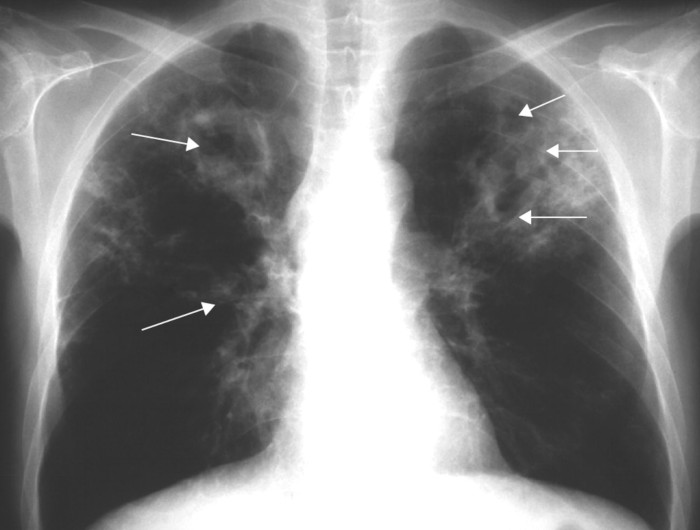

Secondo la MUMedicina Ufficiale la tubercolosi o TBC, è una malattia infettiva causata da vari ceppi di micobatteri, in particolare dal Mycobacterium tuberculosis, chiamato anche Bacillo di Koch. La tubercolosi attacca solitamente i polmoni, ma può colpire anche altre parti del corpo. Si trasmette per via aerea attraverso goccioline di saliva emesse con la tosse. La maggior parte delle infezioni che colpiscono gli esseri umani risultano essere asintomatiche, cioè si ha un'infezione latente. Circa una su dieci infezioni latenti alla fine progredisce in malattia attiva, che, se non trattata, uccide più del 50% delle persone infette.

I sintomi classici sono una tosse cronica con espettorato striato di sangue, febbre di rado elevata, sudorazione notturna e perdita di peso.